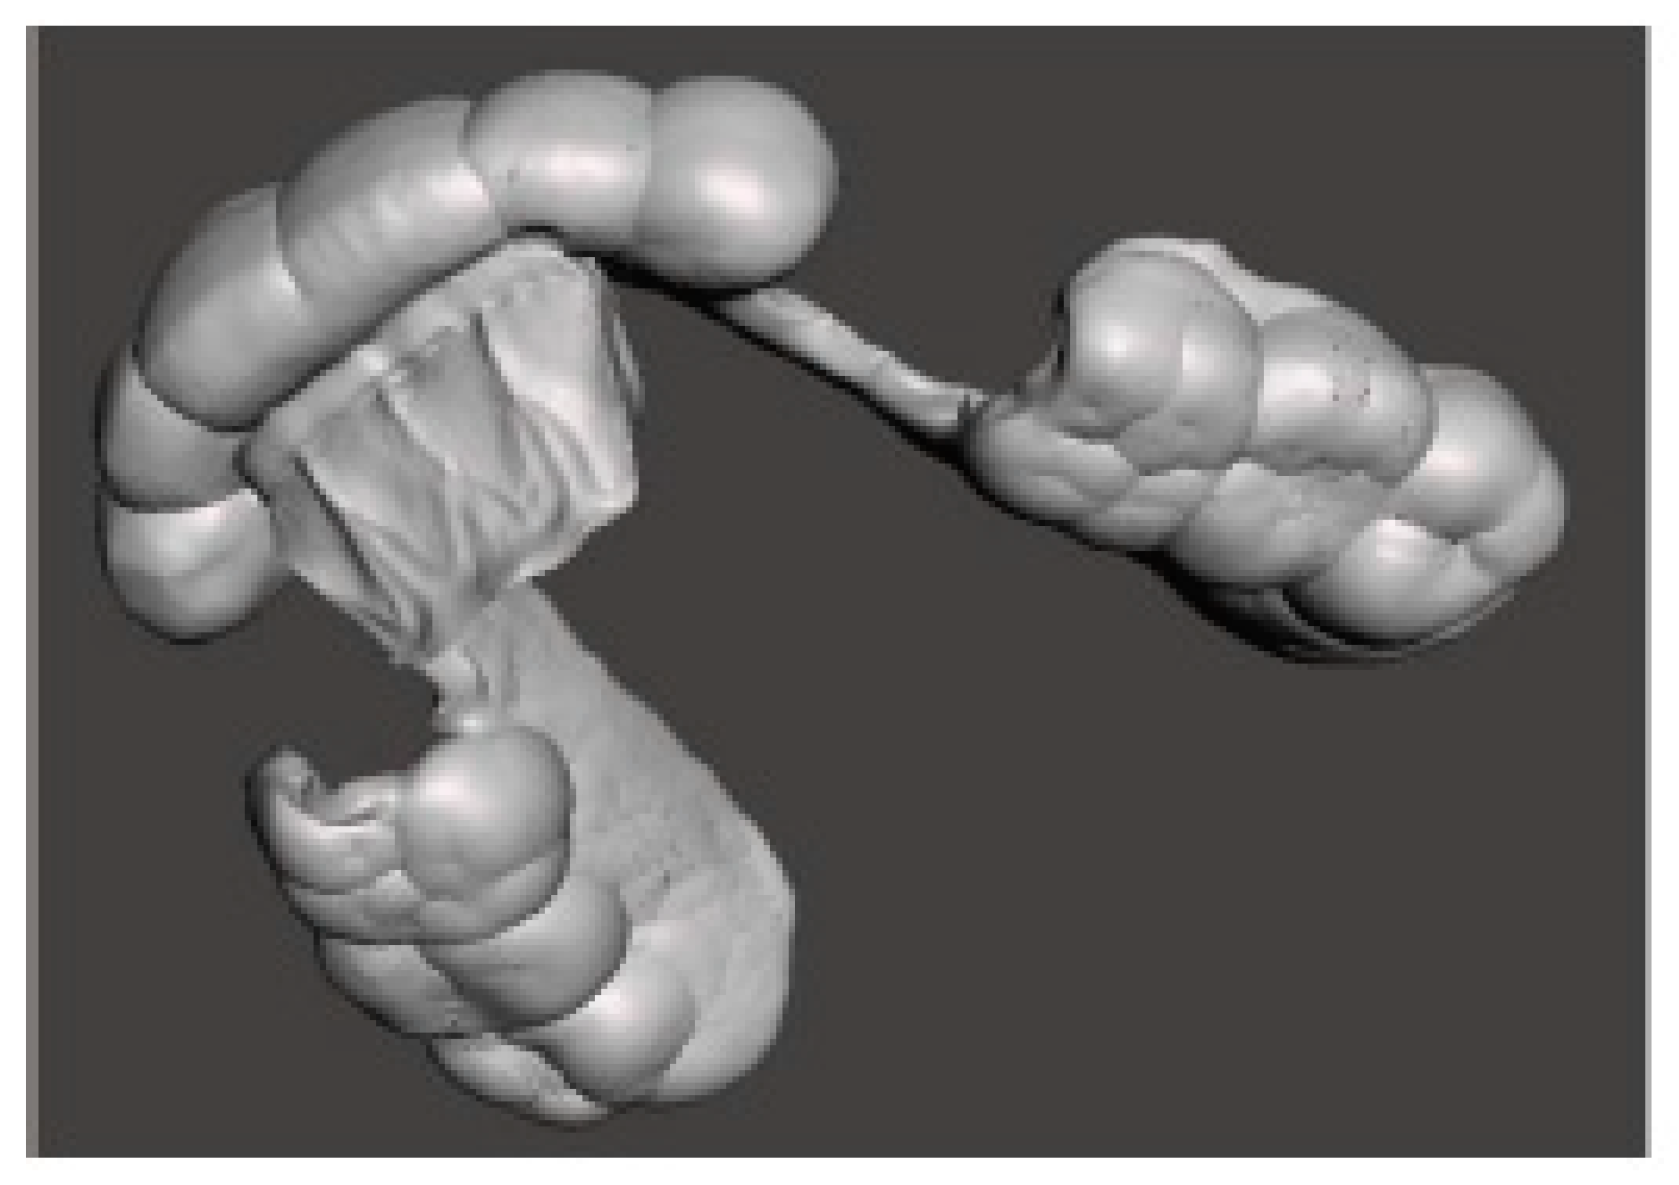

Today, digital technology can come to help clinicians for this purpose, as it allows previsualization of the condylar position and its movements—both in the habitual intercuspation and after its repositioning—allowing a more “rational” choice of a stable mandibular position to plan the entire treatment. This is possible through the preliminary evaluation of the kinematic activity of the mandible by using a recently developed technological device (Tech in motion™, ModJaw, Villeurbanne, France) that uses a digital camera and reproduces real mandibular movements on the. STL files of the arches. These are useful to evaluate condylar tracings, improve the accuracy of the diagnosis, and make the design of an oral appliance ideally customized from the functional aspect. This device is available thanks to the development of two sectors of technological research: that linked to the recording of movements using a sophisticated camera based on 3D stereophotogrammetry (Figure 1), and that concerning visualization of digital models of the dental arches, which can also be matched with the Cone Beam Computed Tomography (CBCT) of the patient (in the most recent version 4.0 of ModJaw), integrating the kinematic evaluation with the visualization of the temporomandibular joints (TMJ) and increasing the precision and predictability of the result in complex cases.

Figure 1. The ModJaw device with a camera based on 3D stereophotogrammetry to record mandibular movements on STL models.